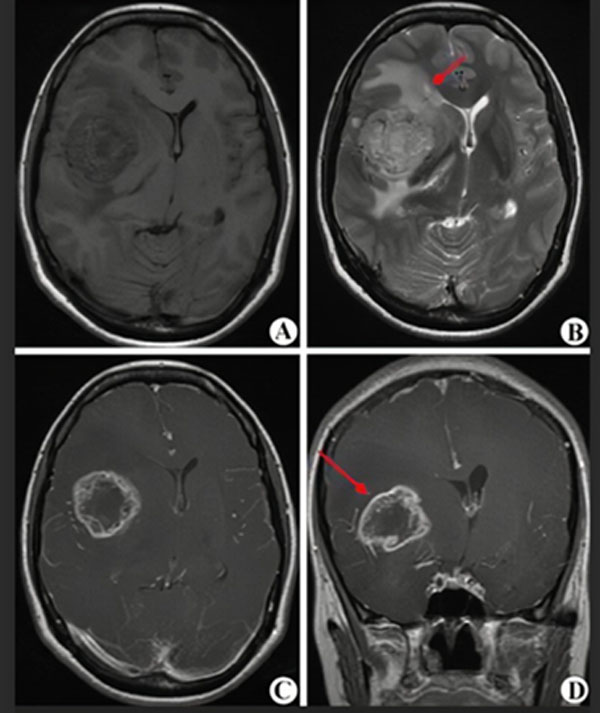

MRI(核磁共振)是一种无创伤的影像学检查,对脑肿瘤敏感性较高,大约1-2天可以拿到结果,是诊断和评估治疗效果的首选但准确性只有80%-90%,不能作为确诊的最终依据。

(图A-D显示为高级别胶质瘤的核磁表现,红箭头指示肿瘤所在)

胶质瘤最终确诊还要靠立体定向穿刺或开颅手术等有创操作,取得病变组织,由病理科医生确认病变是否为胶质瘤以及胶质瘤的级别,这一过程大约需要7-10天。